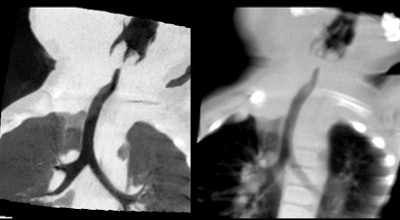

| Nearly whole-body imaging in a single rotation reveals lung changes and pleural thickening. |